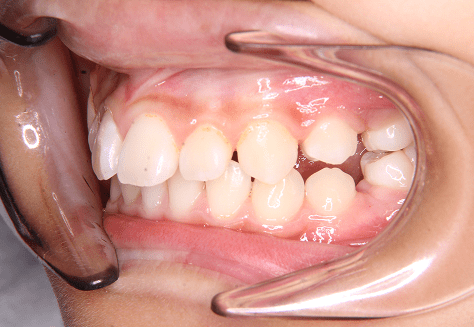

H.A

治療前

治療後

主訴

正中がずれているのが気になる。ちゃんと噛めていない。

診断

上下両側第二小臼歯先天欠如・上顎前突

年齢/性別

10代/女性

抜歯部位

必要に応じて乳歯抜歯

使用装置

6か月間エッジワイズにて下顎第一大臼歯の近心傾斜改善→上下インビザラインへ移行

保定装置

上下ビベラリテーナー

診察料金

ワイヤー時:5,500円×4回

インビザライン時:1,100円×21回 -

治療期間

2年4カ月